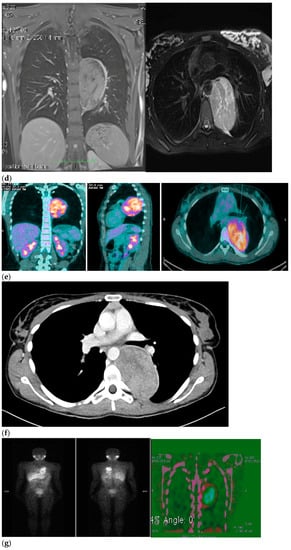

Therefore, her GP prescribed a chest X-ray, which revealed a voluminous opacity in her posterior mediastinum on the left (Figure 1a); subsequently, the GP referred the patient to a thoracic surgeon, who prescribed a series of imaging (Figure 1b–h) tests to biologically circumscribe the lesion, in order to evaluate its metabolic activity and its eventual malignancy. After these further investigations, the patient’s histopathological diagnosis was of poorly differentiated neuroblastoma ALK + (IIC), I stadium [,]. The patient was inserted in the operating room schedule for surgical excision.

Figure 1.

(a–h) Imaging assessments for pre-surgical evaluation. (a) X-ray scans. (NOTE: Voluminous opacity in the posterior mediastinum on the left, with a major axis of about 12 cm). (b) Thorax CT scan with Iodixanol. (NOTE: Solid, oval-shaped tumour in the left posterior mediastinum, measuring 8 × 5.5 cm. Anteriorly, the mass pressed the left main bronchus from behind, while medially it displaced the thoracic aorta—sitting directly on the metamers T5 to T8, and compressing the hemiazygos vein. The mass also went through the intervertebral foramen, between T6 and T7, and partially through the VI and VII intercostal spaces; laterally, it caused dystelectasis of the lung parenchyma. The NB had an irregular density, with innumerable small foci of calcification, and areas of slightly blurred impregnation of the contrast medium). (c) Tracheobronchoscopy. (NOTE: Left lower lobe bronchus with a luminal narrowing, resembling an extrinsic compression. In detail: left lower lobe bronchus, left main bronchus, trachea and carina). (d) Thorax MRI with Gadoteridol. (NOTE: Presence of a mass with maximum dimensions of approximately 7.5 × 5.5 cm axially and 10 cm of craniocaudal extension, limited by a plane passing from upper T6 to lower T9. Extension up to the ipsilateral lung, which caused a moderate compression and a slight compressive effect, also on the left sections of the heart (in particular the atrium). Slight anterior displacement of the ipsilateral pulmonary hilum structures; the neoplasm also came into contact with the aorta. The tumour went through the left T6–T7 intervertebral foramen—taking up space at the foraminal level, not at the level of the spinal canal—and it also extended up the corresponding intercostal space; it was compatible with a lesion originating from the nerve sheath arising from the T6–T7 foraminal region). (e) Total-Body PET/CT. (NOTE: Presence of an increased glucose metabolism lesion in the posterior mediastinal area, showing a necrotic portion and a metabolically more active portion, located in the medial side and infiltrating the posterior arch of the 6th left rib). (f) Thorax CT scan with Lopromide. (NOTE: Minor volumetric increase of the known space-occupying lesion, which maintained similar densitometric characteristics, clear limits, and maximum diameters equal to 8.5 × 6 cm on the transverse plane, with a maximum longitudinal extension of 11 cm. The solid component which went through the intercostal space between T6 and T7 was substantially unchanged. Absence of pleural or pericardial effusion). (g) Total-body scintigraphy with metaiodobenzylguanidine. (NOTE: The examination confirmed that the neoplasm was confined to the mediastinum only. The area of greater contrast medium enhancement corresponded to the left hemithorax, in particular, to the left posterior mediastinal region, from T6 to T9). (h) Thorax MRI with Gadoteridol. (NOTE: Slight increase in size of the known space-occupying lesion in the posterior mediastinum (85 × 60 × 103 mm vs. 80 × 55 × 100 mm). At T6–T7 level, the mass occupied some left foraminal canal space. Next to the known lesion, pleural effusion thin layer (maximum thickness of 11 mm)).